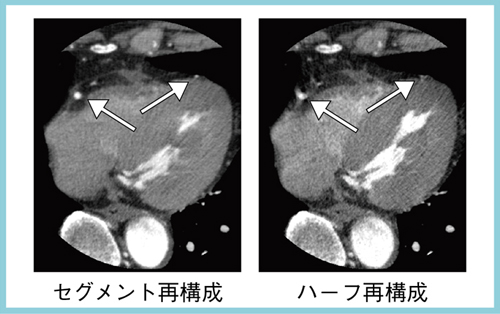

高心拍症例では,時間分解能の向上のために,セグメント再構成を使った撮影を行う。Aquilion ONEでは,従来のマルチスライスCTとは異なり,どの位置でも同じタイミングのスキャンデータから画像再構成を行うため,セグメント再構成でも時相の相違によるアーチファクトがない画像を得ることができる。図2は,左側がセグメント再構成,右側がハーフ再構成の画像で,同じ生データからの再構成だが,セグメント再構成の方がRCAやLADの分枝がブレなく描出されている。セグメント再構成法は,320列のようなボリュームスキャンが可能な装置において,最も威力を発揮する再構成法だと考えられる。

図2 Aquilion ONEでのセグメント再構成とハーフ再構成の比較